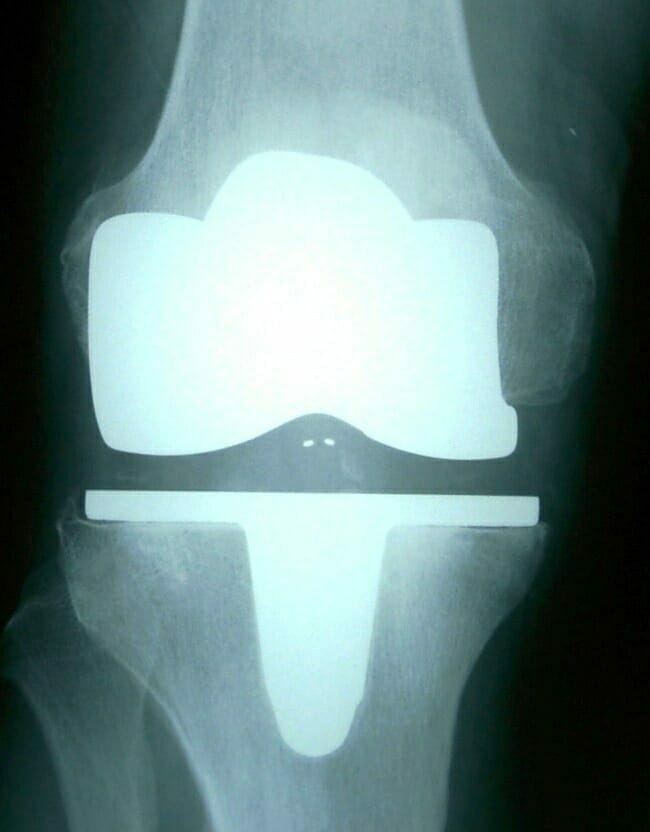

Investigations for arthritis usually entail weight-bearing radiographs of the knee and also a long leg standing alignment x-ray of the leg to show the axes of the leg and knee.

AP x-ray of the knee showing gross lateral compartment osteoarthritis with total loss of lateral joint space.